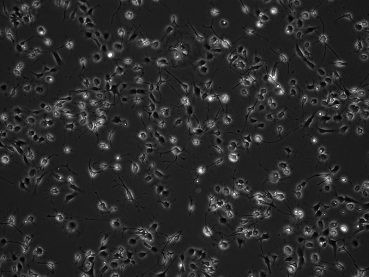

Patient-derived pediatric PFA ependymoma cell lines grown under hypoxic conditions display distinct morphologies (10X).

Patient-derived paediatric PFA ependymoma cell lines grown under hypoxic conditions display distinct morphologies (10X).